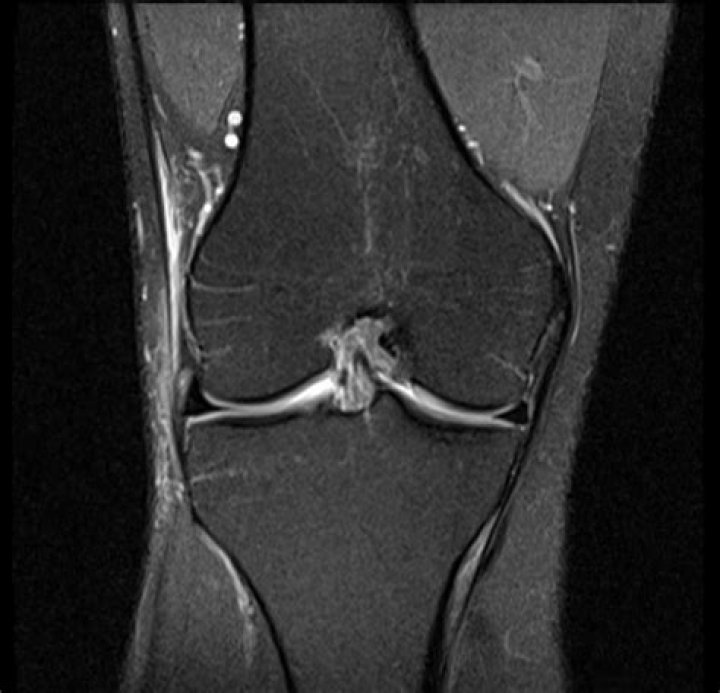

In severe cases, magnetic resonance imaging (MRI) may be helpful in identifying the extent of inflammation of the ITB. Findings on MRI most commonly include thickening of the ITB in the region overlying the lateral femoral condyle and fluid collection underneath the ITB at this area. See the image below.